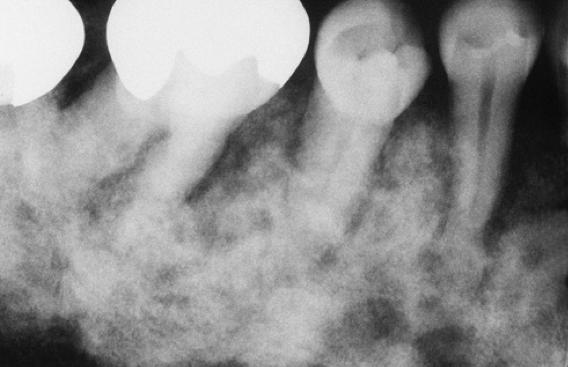

What is the likely Dx?

Paget’s disease. cotton wool appearance and hypercementosis.